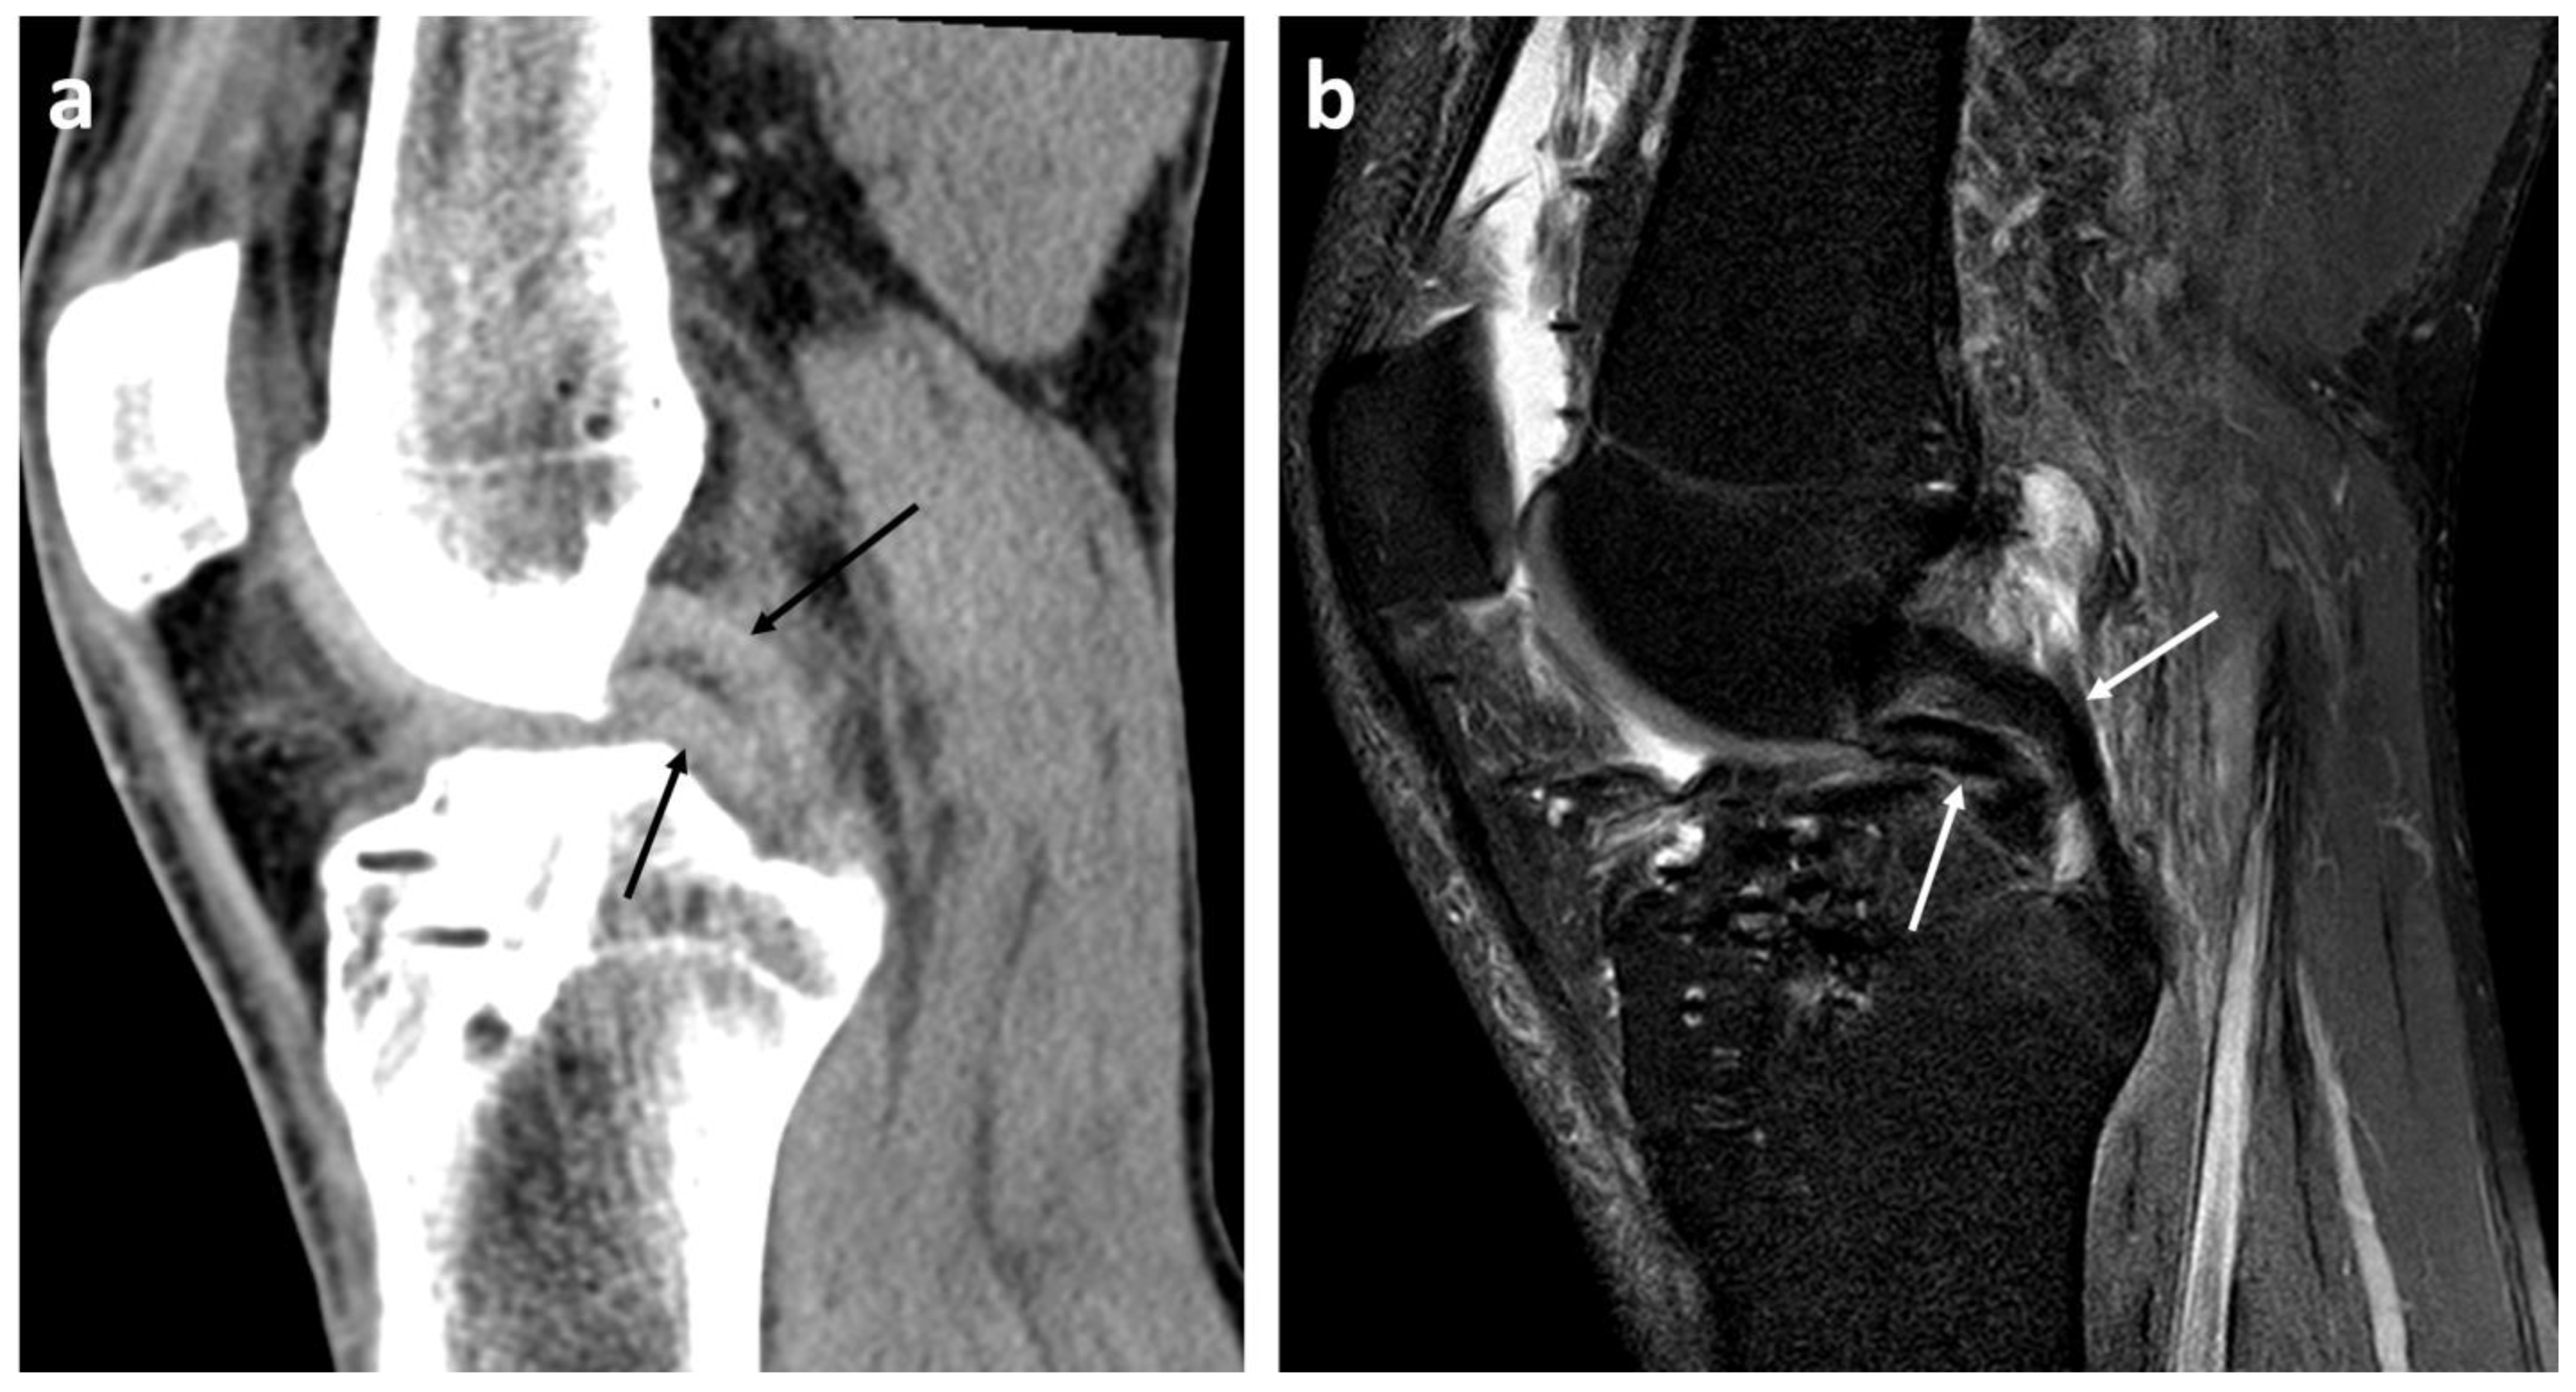

23 years old male with bucket handle tear of medial meniscus (A Bucket Handle Tear Double Pcl Sign  The double posterior cruciate ligament (pcl) sign is seen on sagittal mri and can signify a displaced meniscal tear, typically that of the medial meniscus. Diagnosis can be suspected clinically with joint line tenderness and a positive mcmurray's test, and can be confirmed with mri studies. Your doctor can often identify a bucket handle tear because it has a distinct. Bucket Handle Tear Double Pcl Sign.

Displaced buckethandle tear of the medial meniscus. (a) Coronal T2 FSE Bucket Handle Tear Double Pcl Sign  The double posterior cruciate ligament (pcl) sign is seen on sagittal mri and can signify a displaced meniscal tear, typically that of the medial meniscus. Your doctor can often identify a bucket handle tear because it has a distinct “double pcl” sign, where the posterior cruciate ligament (pcl) looks doubled because of the. Diagnosis can be suspected clinically with joint. Bucket Handle Tear Double Pcl Sign.

Displaced buckethandle tear of the medial meniscus. (a) Coronal T2 FSE Bucket Handle Tear Double Pcl Sign  Diagnosis can be suspected clinically with joint line tenderness and a positive mcmurray's test, and can be confirmed with mri studies. The double posterior cruciate ligament (pcl) sign is seen on sagittal mri and can signify a displaced meniscal tear, typically that of the medial meniscus. Your doctor can often identify a bucket handle tear because it has a distinct. Bucket Handle Tear Double Pcl Sign.